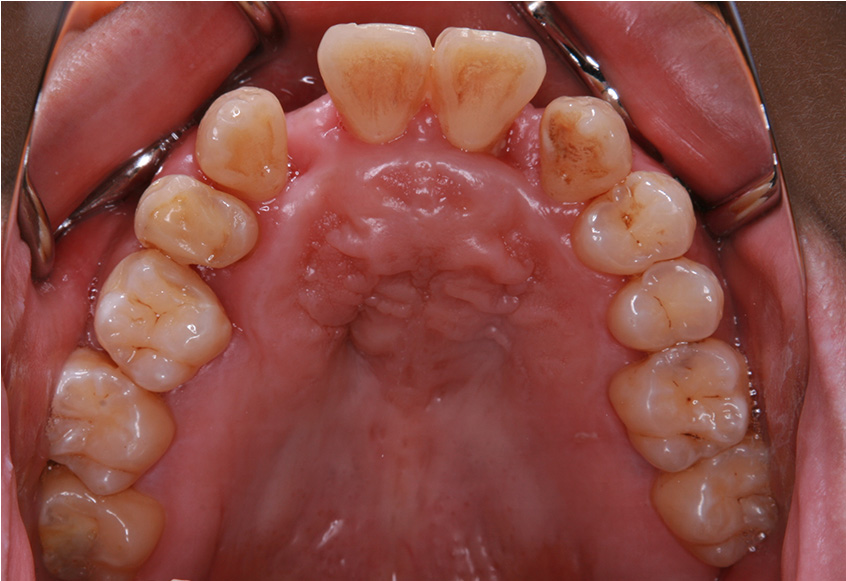

親知らずの痛みがなくなった患者さんは、昔から歯並びが気になっていることを打ち明けてくれました。特に上の歯が少し前に出ていたり、隙間があったりしている点を治したいそうです。そこで、まず上の歯並びの矯正治療を開始しました。

最初のお口の中 ワイヤー装着して治療を開始

| 治療内容 | 上顎側切歯を2本抜歯した後、上顎の歯にブラケットを装着し、ワイヤー、矯正用ゴムで歯の移動を行いました。その後、被せ物の治療を行って治療を終了しています。 |